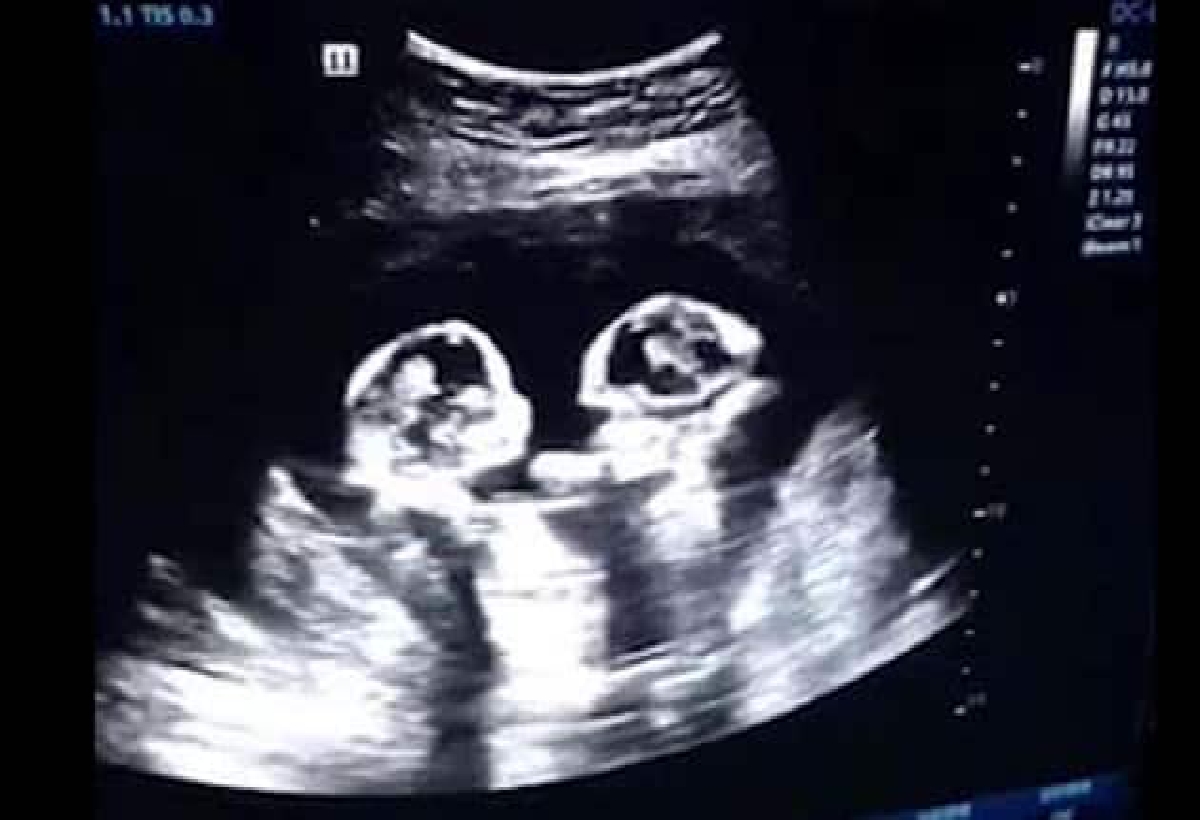

- يعتبر التصوير بالموجات الفوق صوتية (السونار) هي احد اكثر الطرق دقة في حال التشخيص المبكر للحمل بالتوائم.

- الكشف بالأشعة السينية، أو في الأمواج الفوق صوتية (السونار).

- يعد الكشف بالسونار أحد الأساليب المضمونة بالكشف عن حالات الحمل بتوأم، خصوصا عقب 6-8 أسابيع من بدء الحمل.

- فعلى الأغلب يظهر التوأم بشكل واضح من الأسبوع السادس، وقد يتأخر معرفة النوع للجنين حتى الأسبوع العاشر أو الثاني عشر.